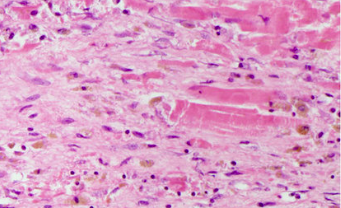

When would this histopatholigcal slide from an MI likely to have occurred

Less than 1 day

Less than 7 days

1-3 week

3-6 weeks scarring occurring